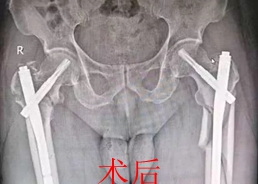

经患者家属同意后,髋股膝胫科专家团队为刘老伯精心制定了严谨的手术及快速康复方案。经过紧张有序的术前准备,在麻醉科、手术室的通力协作下,由黄才平主任为首,在李志勇、邓亚军医师的配合下,为刘老伯行“右股骨粗隆粉碎性骨折闭合复位PFNA内固定术﹢左股骨上段粉碎性骨折闭合复位加长型PFNA内固定术”。手术历时两个半小时,出血量仅200毫升,手术非常成功。

据髋股膝胫科主任、副主任医师黄才平介绍,双侧股骨骨折手术要求手术医师必须做好充分的术前准备,术中要有熟练的配合技巧。随着科技的进步,材料的更新,手术不断微创化, PFNA内固定治疗老年人股骨粗隆间骨折,具有手术创伤小、出血少、骨量缺失少、固定牢靠、术后下床活动早、骨折愈合快、并发症少等优点,是高龄股骨粗隆骨折患者理想的治疗方案。近年来,该科室每年成功救治100余例高龄股骨骨折患者,取得良好的社会效益。